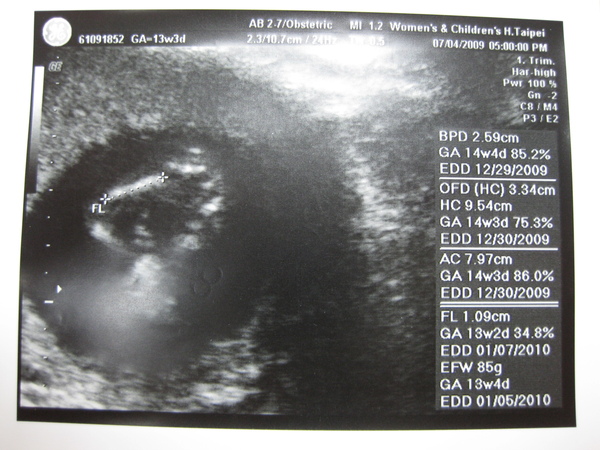

2009.07.04 婦幼醫院 頸部透明帶 14W_4D